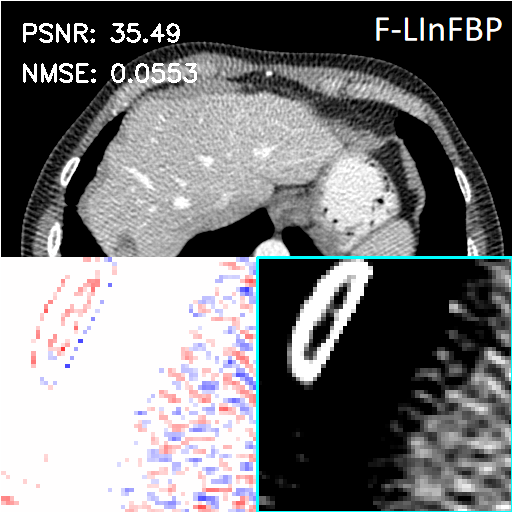

We assess the reconstruction performance of LInFBP under quarter-view cases, i.e., only quarter-view and quarter-view with quarter-dose conditions. Fig. 4 and Fig. 5 present the reconstructed CT images using Li FBP-R, Li FBP-H and our methods at quarter-view cases and quarter-view with quarter-dose cases, respectively. It can be observed from the visualizations that the proposed methods yield better results closer to the ground-truth with higher PSNR scores at all the cases, as indicated by the red circles and arrows in the error maps, compared to Linear FBP methods. Specifically, in Fig. 5, both F-LInFBP and L-LInFBP can reconstruct highly accurate structure textures with negligible artifacts compared to the ground-truth. The improvements in image quality can be ascribed to the accurate radon transform interpolation obtained by the LInFBP, which implies its effectiveness in low-dose CT imaging applications while maintaining image quality. It should also be noted that the L-LInFBP produces almost similar reconstruction performance with F-LInFBP, as seen in the least absolute errors compared to the ground-truth. This indicates that the linear basis functions in L-LInFBP can already represent the continuous backprojection in satisfactory accuracy while with evidently less complexity as compared to F-LInFBP.

For quantitative evaluation, Table 2 presents the quantitative measurements of the CT images reconstructed by the FBP algorithms with different interpolation strategies and the F-LInFBP and L-LInFBP methods at only quarter-view and quarter-view with quarter-dose conditions, respectively. It is seen that both the proposed F-LInFBP and L-LInFBP consistently achieve higher PSNR scores, lower NMSE scores, and higher FSIM scores for all the quarter-view cases and quarter-view with quarter-dose cases compared to other competing methods. And the L-LInFBP can obtain similar quantitative measurements with the F-LInFBP, which is consistent with the visual inspection.